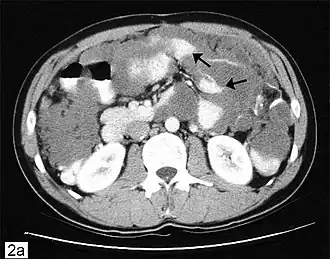

Deze ziekte wordt vaak ontdekt tijdens chirurgie voor andere aandoeningen, bijvoorbeeld hernia-reparatie, waarna een ervaren patholoog de diagnose kan bevestigen. Geavanceerde stadia kunnen zich voordoen als tumoren die voelbaar zijn op de buik of uitzetting van de buik ("gelei-buik" wordt soms gebruikt als een vakterm voor de aandoening). Vanwege de zeldzaamheid van deze ziekte is het belangrijk om een nauwkeurige diagnose te verkrijgen, zodat een passende behandeling kan worden verkregen van een chirurgisch oncoloog die gespecialiseerd is in appendixkanker. Diagnostische tests kunnen CT-scans, onderzoek van weefselmonsters verkregen via laparoscopie en de evaluatie van tumormarkers, zoals CEA en CA-19-9 uit bloedonderzoek, omvatten. In de meeste gevallen is een colonoscopie ongeschikt als diagnostisch hulpmiddel omdat in de meeste gevallen appendixkanker de buikholte binnendringt, maar niet de dikke darm (verspreiding in de dikke darm wordt echter af en toe gemeld). PET-scans kunnen worden gebruikt om hoogwaardig slijmerig adenocarcinoom te evalueren, maar deze test is niet betrouwbaar voor het detecteren van laagwaardige tumoren omdat deze de kleurstof niet opnemen die op scans verschijnt. Nieuwe MRI-procedures worden ontwikkeld voor ziektemonitoring, maar standaard MRI's worden meestal niet gebruikt als diagnostisch hulpmiddel. De diagnose wordt bevestigd door pathologie.